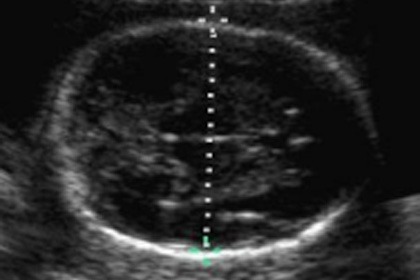

顛倒金字塔的產前檢查模式

在19世紀,我們並沒有掌握的產前診斷和以及提供解決治療方法。孕期保健,僅限於生產時間而且為富人保有的。在20世紀開始,孕產婦和嬰兒死亡率高,從而刺激設立機構提供的...